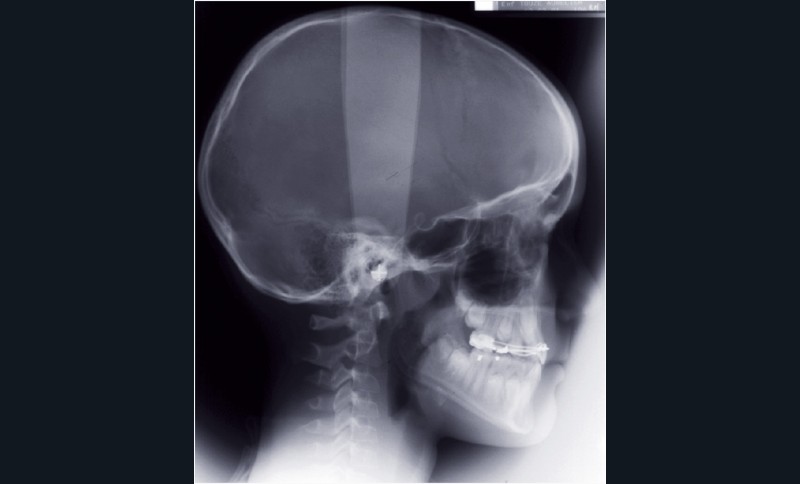

Le bilan radiographique (fig. 6) par l’analyse architecturale de Delaire et l’analyse dento-squelettique confirme l’examen clinique et conduit au diagnostic radiologique suivant :

• pas de prédisposition de la base du crâne à la classe III,

• rétromaxillie,

• brachymaxillie avec petite brachyprémaxillie,

• linguoversion incisive maxillaire,

• légère prognathie mandibulaire par dolichocorpie.

Cette étape de traitement a permis la normalisation des rapports cranio-maxillo-mandibulaires (fig. 10).